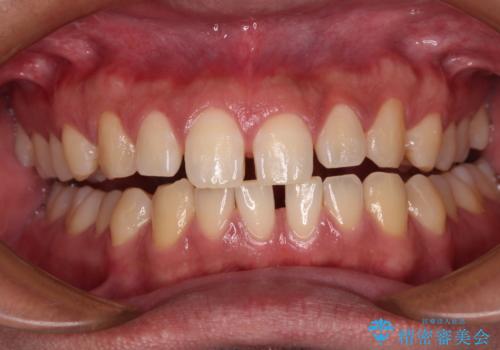

- 上下前歯の叢生を気にして来院された患者様です。

費用を抑え、期間もあまりかけずに治療をしたいとのことで、インビザライン・ライトを用いて矯正治療を行うこととしました。